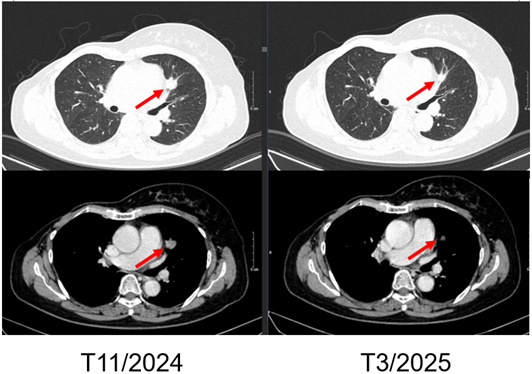

Hình 1. Hình ảnh chụp CT ngực trước điều trị: Tổn thương tái phát thành ngực

Hình 7. Hình ảnh chụp CT ngực trước và sau điều trị: Tổn thương tái phát thành ngực

Hình 8. Hình ảnh chụp CT ngực trước và sau điều trị: Tổn thương phổi trái

– Chụp cắt lớp vi tính ngực:

+ Thành ngực phải có nốt đặc đường kính 5mm – theo dõi tổn thương tái phát

+ Phổi phải: nhu mô thuỳ giữa và dưới có các khối – nốt đặc, lớn nhất 7x8mm

+ Phổi trái: nhu mô thuỳ trên và đáy phổi sát màng phổi có các khối nốt đặc, lớn nhất 9x8mm